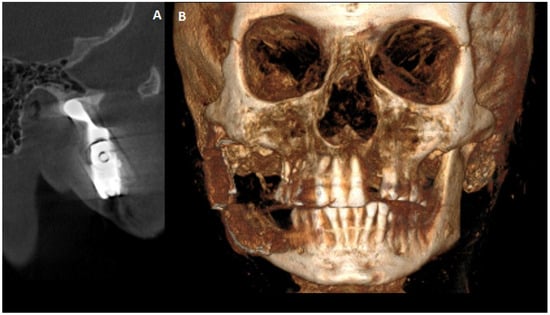

Figure 3. CBCT scans in axial projection (A) with maxillary destruction and sagittal (B) visualization of the cystic destruction of the right condylar process and condylar head. Cystic destruction of the left maxillary bone with an extra bone spread towards the lip and nasal cavity, and right mandibular ramus swelling with proliferation towards the condylar head is noted (white arrows). In surgical planning, the condition of the bone is very important for a good radiological bone evaluation, as well as for cortical bone estimation. Secondly, each surgery must maintain each patient’s quality of life (QOL). In the case of a 69-year-old patient, the most troublesome factors were related to an inability to fully open their mouth, the occurrence of transient pain, inflammation, the presence of right preauricular swelling, and the deterioration of chewing and biting ability. The first surgery step was used to remove all small lesions, fill them with allogenic bone grafts, and perform a right-sided coronoidectomy with cyst removal and decompression to prepare the right condyle for the second stage of surgery. The main troublesome course of surgery included the necessity to remove part of the bone TMJ structures affected by the disease and reconstruct the TMJ for the best possible outcome to enable the elderly lady to be able to properly open her mouth, eat, and speak. Because of this patient’s economic means and a great fear of a total TMJ artificial endoprosthesis, a decision was made to reduce both the costs and scope of surgery, meaning a reduction in the usage of many materials and foreign body components from a custom-made TMJ endoprosthesis. Secondly, since the OKC did not do any destruction within the condylar fossa, the articular disc and TMJ joint were healthy, so the usage of an acetabulum, namely the glenoid fossa alloplastic component, was not necessary. Planning a good CBCT is enough to plan the scope of bone resection and removal of all polycystic lesions from the right mandibular head, condyle, and part of the ramus. Because of the locally aggressive character of OKC, their extracortical spread, polycystic occurrence, and joint manifestation, a decision was made for more aggressive surgery with immediate joint reconstruction in the second stage of surgery when mouth opening was improved. Both surgeons (K.N., K.Ł.) decided to improve the overall mouth opening and excise all advanced aggressive OKC lesions at first, and then decide on the scope for TMJ surgery to improve occlusion and bite, and prepare for further patients’ prosthodontic treatment. No necessity for additional CT, MRI, or similar studies was needed.